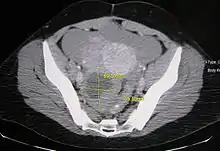

Ovarian cysts are usually diagnosed by ultrasound, CT scan, or MRI, and correlated with clinical presentation and endocrinologic tests as appropriate.[10]